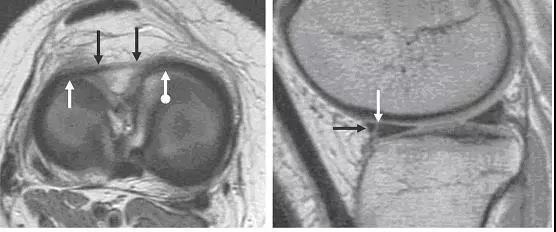

图 2 正常半月板

左图:外侧半月板,由于横截面面积一致,故在MRI 上可见外侧半月板前后角(纵向白色箭头)形状和大小较相似。上下腘肌半月板纤维束(黑色箭头)在外侧半月板后角处,形成裂孔,中间有腘肌腱(水平白色箭头)通过。右图:内侧半月板,可见后角(白色圆箭头),略大于前角(白色直箭头)